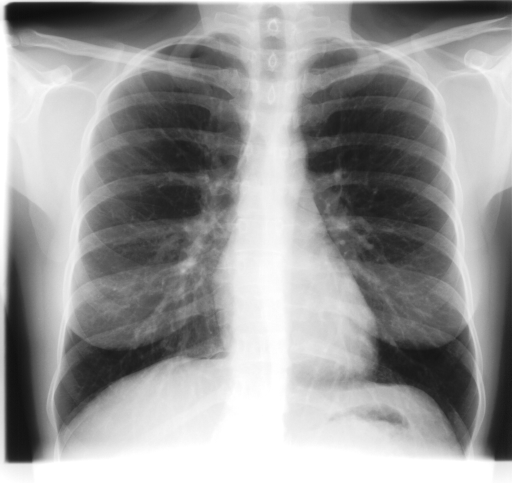

In this section, we report two series of experiments. The first one verifies the correctness or reliability of the micro-DE algorithm to find optimal projections compared to an exhaustive search when we are looking for 4 optimal projection angles out of 16 equidistant angles. In the second experiments, we still provide the results for exhaustive 4/16 selection but examine the evolutionary approach to get 4/180 and 8/180 to investigate the reconstruction accuracy of the micro-DE via correlation of the input image and the reconstructed image using 4/16 (exhaustive), 4/180 (micro-DE) and 8/180 (micro-DE). To conduct the experiments we used 50 images from IRMA dataset [34, 35], a benchmarking collection of 14,400 x-rays images. We selected 10 random classes out of 58 classes, and for each class, we randomly drew 5 images to be used in our experiments. Figure 4 shows the images we have used.

![]() |

[34∘, 79∘, 124∘, 158∘] with |

| [45∘, 79∘, 124∘, 146∘] with | |

[0∘, 79∘, 101∘, 157∘] with |

| [0∘, 68∘, 112∘, 169∘] with | |

Radon barcodes are binarized versions of Radon projections. To create the optimal Radon barcodes (barcodes that are highly expressive to tag digital images in a unique way such that they can be retrieved easily), one has to find the optimal projections. Since we are trying to find projections, we should find a fitness function that guides micro-DE in the right direction. If the projections are good (compared to all other possible combinations), then image reconstruction using these projections should yield smaller error compared to all other combinations. Figure 3 shows for the chest x-ray that the 4 best projections by examining all 1820 combinations when 16 equidistant projections are available.